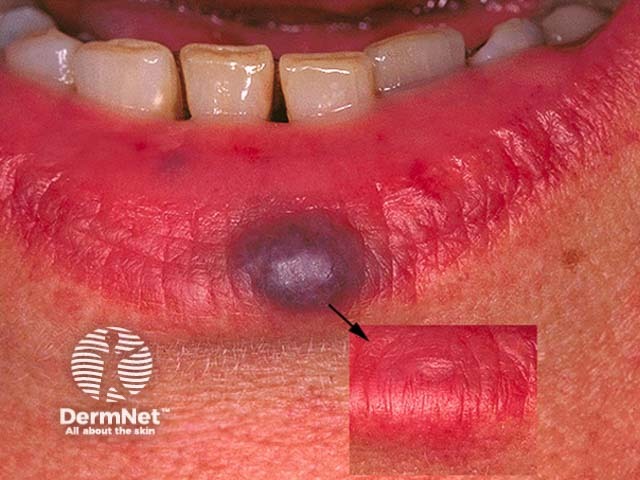

A venous lake is a common bluish soft macule or papule due to vascular dilatation. It is most often seen on the lower lip.

A venous lake is a soft, squashable, blue or purple macule or papule, that is 0.2–1 cm in diameter. Although they may arise anywhere, most venous lakes are diagnosed on the lower lip (on the vermilion margin or mucosal surface), on an earlobe, or elsewhere on the face, neck, or upper trunk.

A venous lake is usually easy to diagnose clinically by its appearance. The colour disappears on compression of the macule or papule due to the clearance of blood from the dilated venule. This is most easily seen using a glass slide or the lens of a contact dermatoscope. A venous lake has a structureless blue or purple appearance on dermoscopy. A biopsy is rarely necessary and shows a dilated venule.